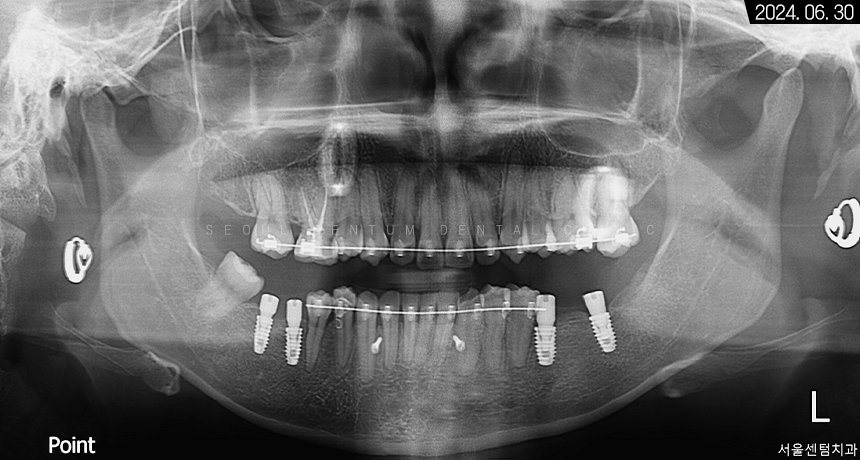

하악 좌측 사랑니 발거 후

임플란트가 필요한 부분들에

픽스처를 견고하게 식립해 드렸습니다.

일정 기간이 지난 후 고정력을 체크하고

지대주에 이어서

크라운까지 예쁘게 수복해 드렸습니다~

크라운으로 감싸고 난 후의 치근단 모습입니다.

정확한 간격으로 견고하게 심어졌으며

주변 치조골 양도 풍부합니다.